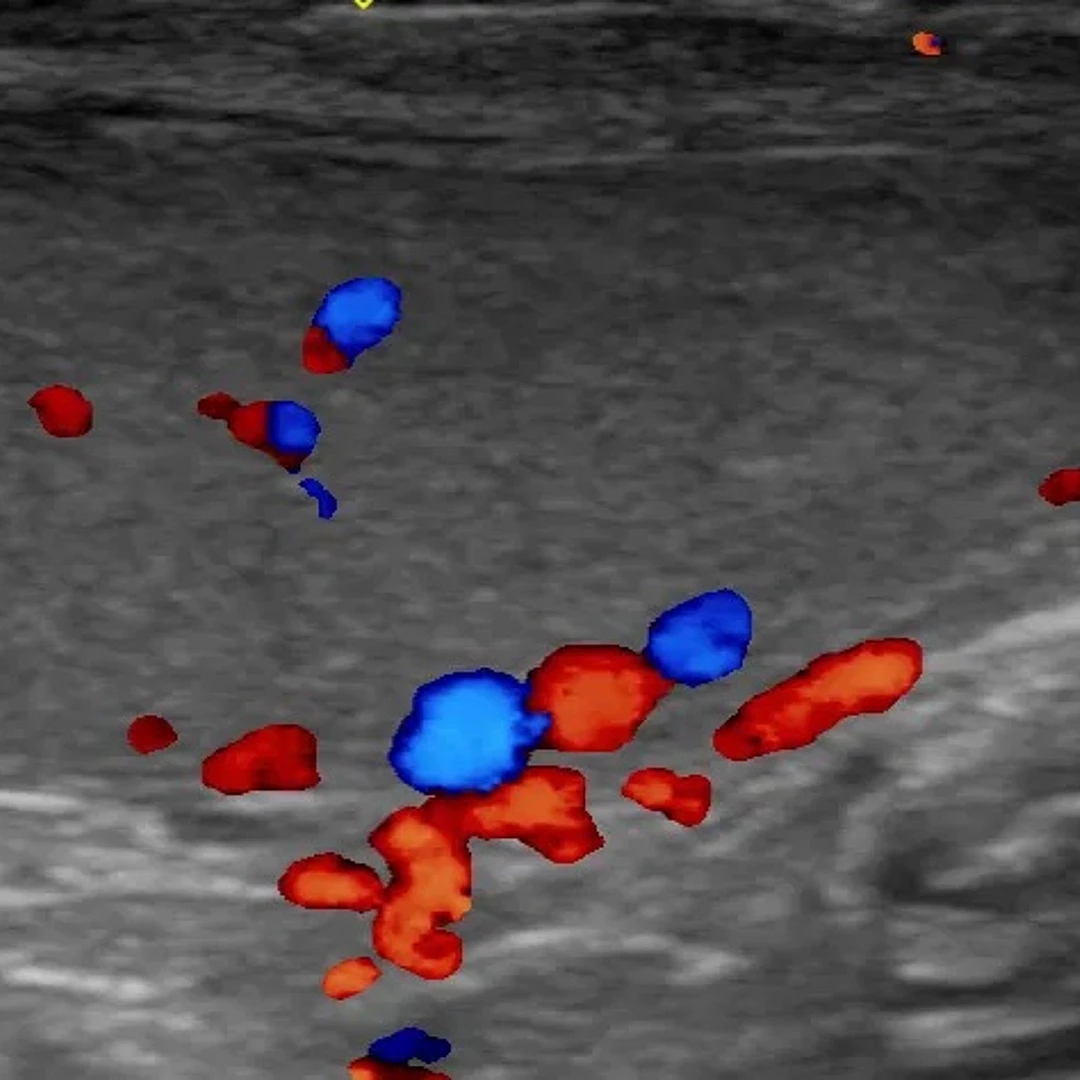

DVT and Vascular Ultrasound

DVT and Vascular Ultrasound assesses blood flow in veins and arteries to detect deep vein thrombosis (DVT) or vascular blockages. It’s a safe, non-invasive method for diagnosing circulatory issues and guiding treatment.